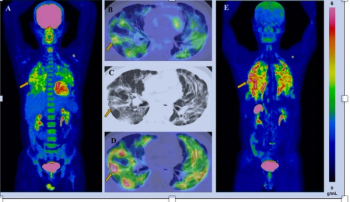

The dual-targeted 177Lu-DOTA-FAPI-RGD reportedly reduced or stopped the growth of cancer lesions in 88.9 percent of advanced adenocarcinomas in a small cohort of patients with varied cancers including pulmonary, pancreatic and ovarian cancer, according to new research presented at the SNMMI conference.